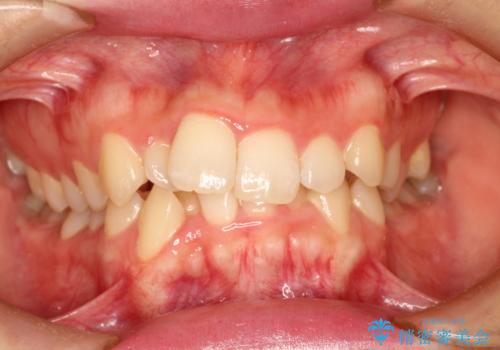

重度の不正咬合 Cl.Ⅱ div.2 を表のワイヤー矯正で綺麗に!

- 右下の第2小臼歯は完全に埋伏していたため、これは歯列に勘定せず計画をたてた

→右側は上顎第1小臼歯の抜歯によるCl.Ⅰ目標

→左側は上顎第1小臼歯抜歯・下顎第2小臼歯の抜歯によるCl.Ⅰ目標

一般的なCl.Ⅱ div.2の治療法に基づき、上顎のフレアアウト後に抜歯を行い、スペースクローズに移行した